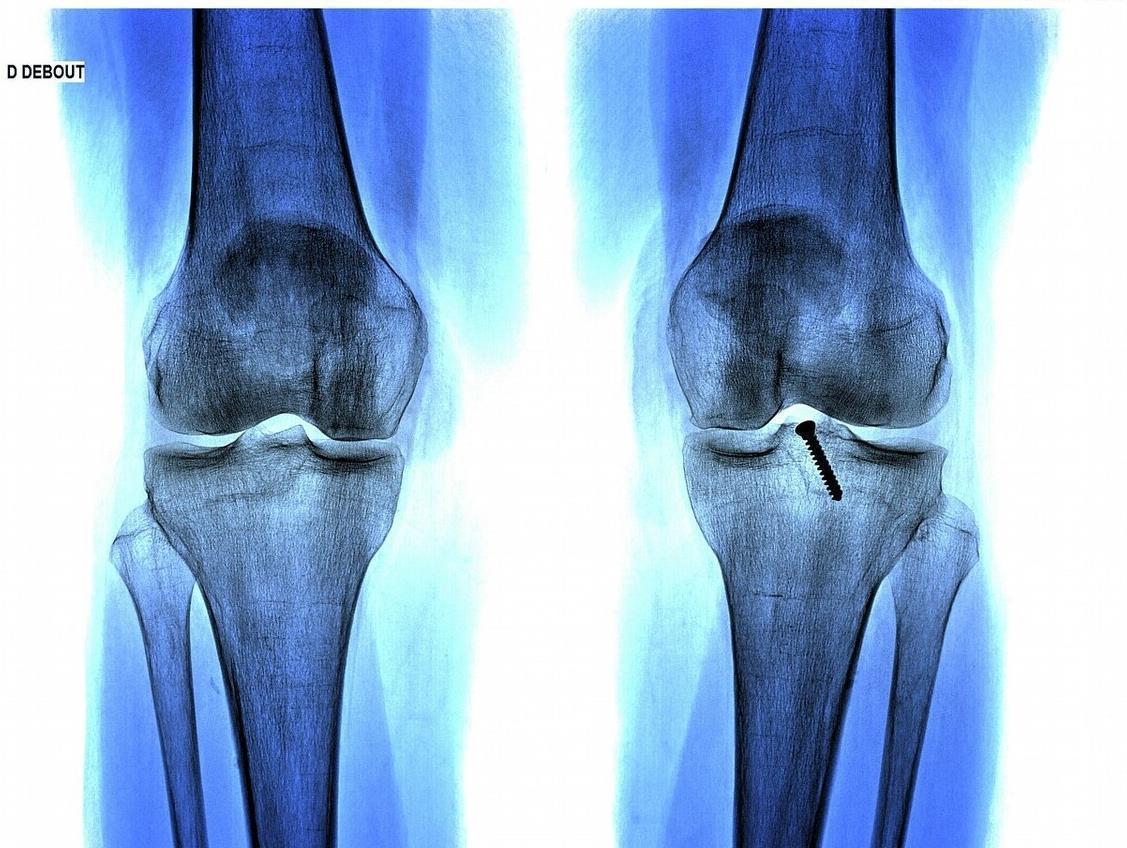

两年过去了,小徐的身高好似没长,十岁的时候就一米四了,现在同龄人都已经一米六多了,足足比别人矮了近20厘米,小徐的妈妈这下坐不住了,急忙带着孩子就去了医院。经医生详细检查,大夫发现小徐的骨垢线已经趋近闭合了,这就意味着小徐已经几乎没有长高的机会了。小徐的妈妈这个时候才悔怨,如果不是她疏忽,早点带孩子来看看,说不定孩子可以健康成长。